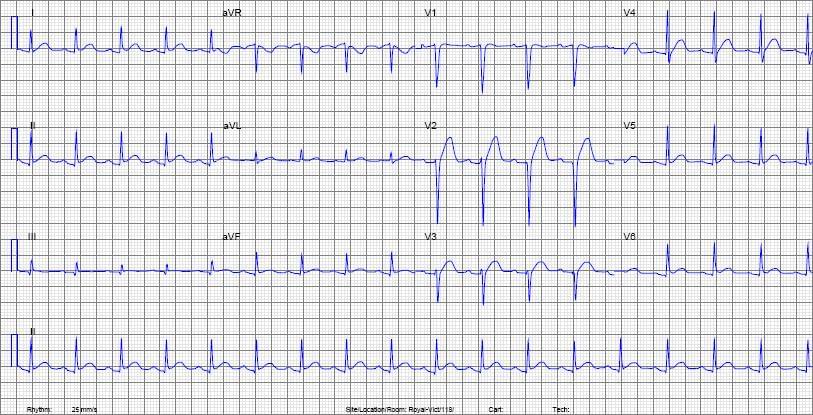

ECG Quiz Home Cardiology 0% 19 votes, 0 avg 137 ECG Quiz This quiz will test your knowledge of ECGs. 15 ECGs are included in this test. Please contact us for a complete test in case you are interested. 1 / 25 1. What is the finding here? A. Sinus arrest B. Mobitz-II AV block C. Complete heart block D. Sinus bradycardia 2 / 25 2. A young patient presented with chest pain aggravating in lying posture. ECG shows features of: A. Acute Lateral wall MI B. Acute Anterior MI C. Pericarditis D. NSTEMI 3 / 25 3. A 60-years-old female patient with diabetes presented to you with severe pain in the epigastric region and dizziness. ECG show these changes. What is your diagnosis? A. Acute Lateral MI B. Acute Inferior MI C. Acute Anterior MI D. Acute Posterior MI 4 / 25 4. What is the ECG diagnosis here? A. Mobitz-II AV Block B. Complete AV Block C. Rate controlled AF D. Mobitz-I AV Block 5 / 25 5. What is the ECG diagnosis A. Sinus Tachycardia B. Supraventricular Tachycardia C. Junctional Tachycardia D. Sinus Rhythm 6 / 25 6. What does this ECG show? A. First degree AV block B. Long QT interval C. Sinus Bradycardia D. Short QT interval 7 / 25 7. This elderly male patient, a known case of IHD, presented with dizziness and syncope. What does this ECG reveal? A. Mobitz II AV Block B. Sinus Bradycardia C. Sick Sinus Syndrome D. Complete Heart Block 8 / 25 8. What is the rhythm abnormality in this ECG strip? A. No abnormality B. Sinus Bradycardia C. Long QT interval D. Wenckebach phenomenon Explanation: The ECG strip shows gradual prolongation of the PR interval followed by a non-conducted P wave. This is Wenckebach Phenomenon or Second degree, Mobitz-I AV Block. 9 / 25 9. What abnormality? A. Ventricular Trigeminy B. Ventricular Premature Contractions (VPCs) C. Ventricular Bigeminy D. Electrical Alternans 10 / 25 10. Patient with severe chest pain and diaphoresis. What is this ECG suggestive of? A. Lateral MI B. Anterolateral MI C. Pericarditis D. Anterior MI 11 / 25 11. This is an ECG of a patient with diabetes and advanced diabetic retinopathy & nephropathy. What is this ECG suggestive of? A. Hypokalemia B. Hyperkalemia C. Hypocalcemia D. Hyponatremia 12 / 25 12. What abnormality is present here? A. 2:1 AV Block B. Mobitz II AV block C. Complete AV Block D. Mobitz I Av block 13 / 25 13. What does this ECG show? A. AF with rapid & aberrant conduction B. VF C. Torsades de pointes D. Monomorphic VT 14 / 25 14. A young patient presented syncope. What is the ECG suggestive of? A. Acute Anterior MI B. Brugada Syndrome C. Early Repolarization D. RBBB 15 / 25 15. What abnormality is present in this ECG? A. Atrial Ectopics B. Sinus Arrhythmia C. Junctional Ectopics D. No abnormality 16 / 25 16. What does the ECG shows? A. Polymorphic VPCs B. Quadrigeminy C. Idioventricular Rhythm D. Monomorphic VPCs 17 / 25 17. The ECG shows A. Complete heart block B. Sinus Bradycardia C. Sinus rhythm D. Prolonged QT interval 18 / 25 18. What does this ECG show? A. AF B. Sinus Tachycardia C. SVT D. Atrial Flutter 19 / 25 19. This ECG is showing A. AF with bradycardia B. Atrial flutter C. Normal ECG D. AF Apparently, there are fibrillation waves, however by looking closely on ECG, QRS complexes are preceded by P waves, Heart rate is around 60 so no bradycardia. 20 / 25 20. What is this ECG consistent with? A. Brugada syndrome B. Hypothermia C. RBBB D. Lateral wall MI The ECG shows J-wave or Osborn waves, more typically seen here in anterior leads. 21 / 25 21. What is the likely diagnosis based on ECG findings A. Acute Pericarditis B. Acute Anterior STEMI C. Left ventricular hypertrophy D. Acute Anterolateral STEMI 22 / 25 22. What is the ECG diagnosis? A. Atrial Flutter with variable block B. Atrial Flutter C. Patient with Parkinsonian tremors D. Atrial Fibrillation with coarse fibrillatory waves Explanation: This ECG shows sawtooth waves (flutter waves) in the majority of leads with irregularly placed QRS waves. Therefore it is suggestive of Atrial Flutter with variable block. Tremors will show abnormal baseline only in limb leads. 23 / 25 23. What is the finding A. Sinus Arrhythmia B. Sinus Rhythm C. Sinus Tachycardia D. Sinus Block 24 / 25 24. Comment what is the cardiac axis in this ECG? A. Normal axis B. Right Axis Deviation (RAD) C. Extreme axis D. Left Axis Deviation (LAD) 25 / 25 25. This ECG is suggestive of A. Hyperkalemia B. Normal ECG C. Acute Anterior STEMI D. Left Ventricular Hypertrophy LinkedIn Facebook Twitter VKontakte Visit our FB page Restart Quiz Send Feedback Previous Post Rheumatology Next Post Endocrinology